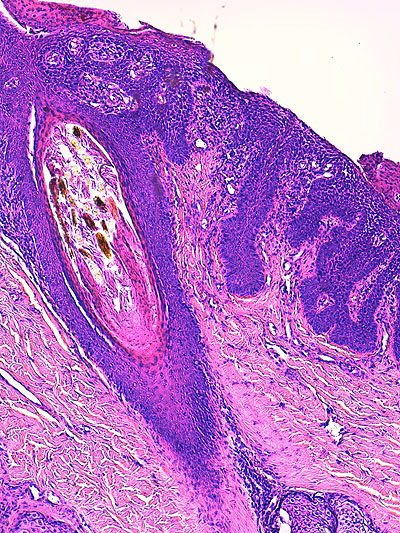

Photo 2 (Hémalun Eosine X 40) : au faible grossissement, l’épiderme revêt un aspect bleu-blanc-rouge,

bleu pour hyperplasie des couches basales, blanc pour vacuolisation des acanthocytes sous-cornés et

rouge pour parakératose de la couche cornée. Le derme est faiblement à modérément inflammatoire.

Légendes de la Photo 2 :

- Flèche bleue : hyperplasie des couches basales

- Flèche blanche : vacuolisation des acanthocytes sous-cornés

- Flèche rouge : pour parakératose de la couche cornée

- Étoile rouge : Le derme est faiblement à modérément inflammatoire